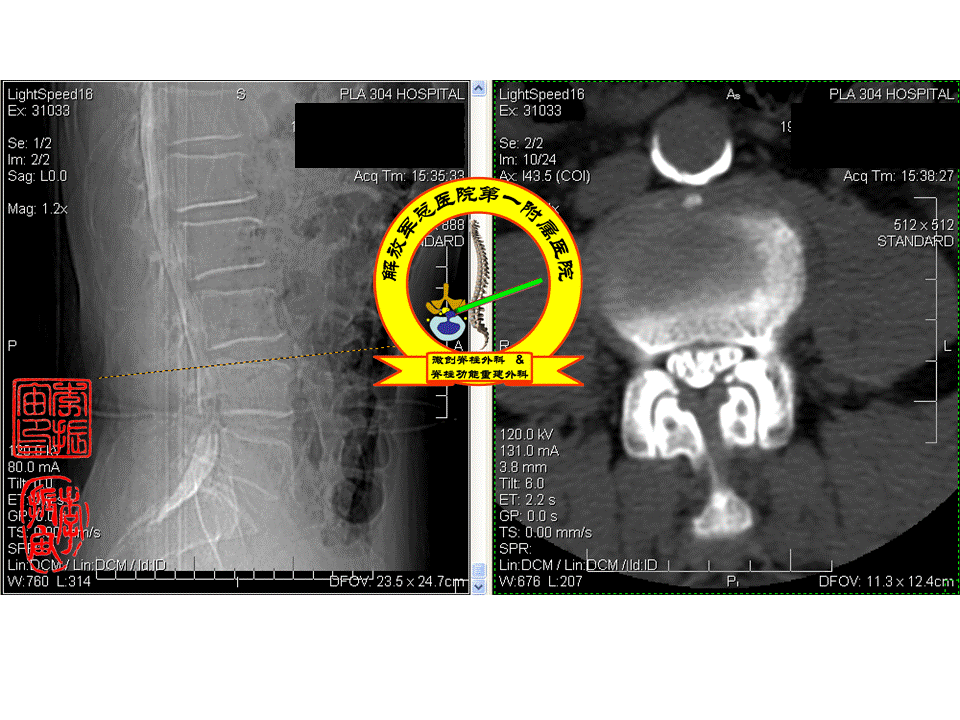

术前腰椎ct提示腰4-5椎管狭窄.

图片尺寸610x456